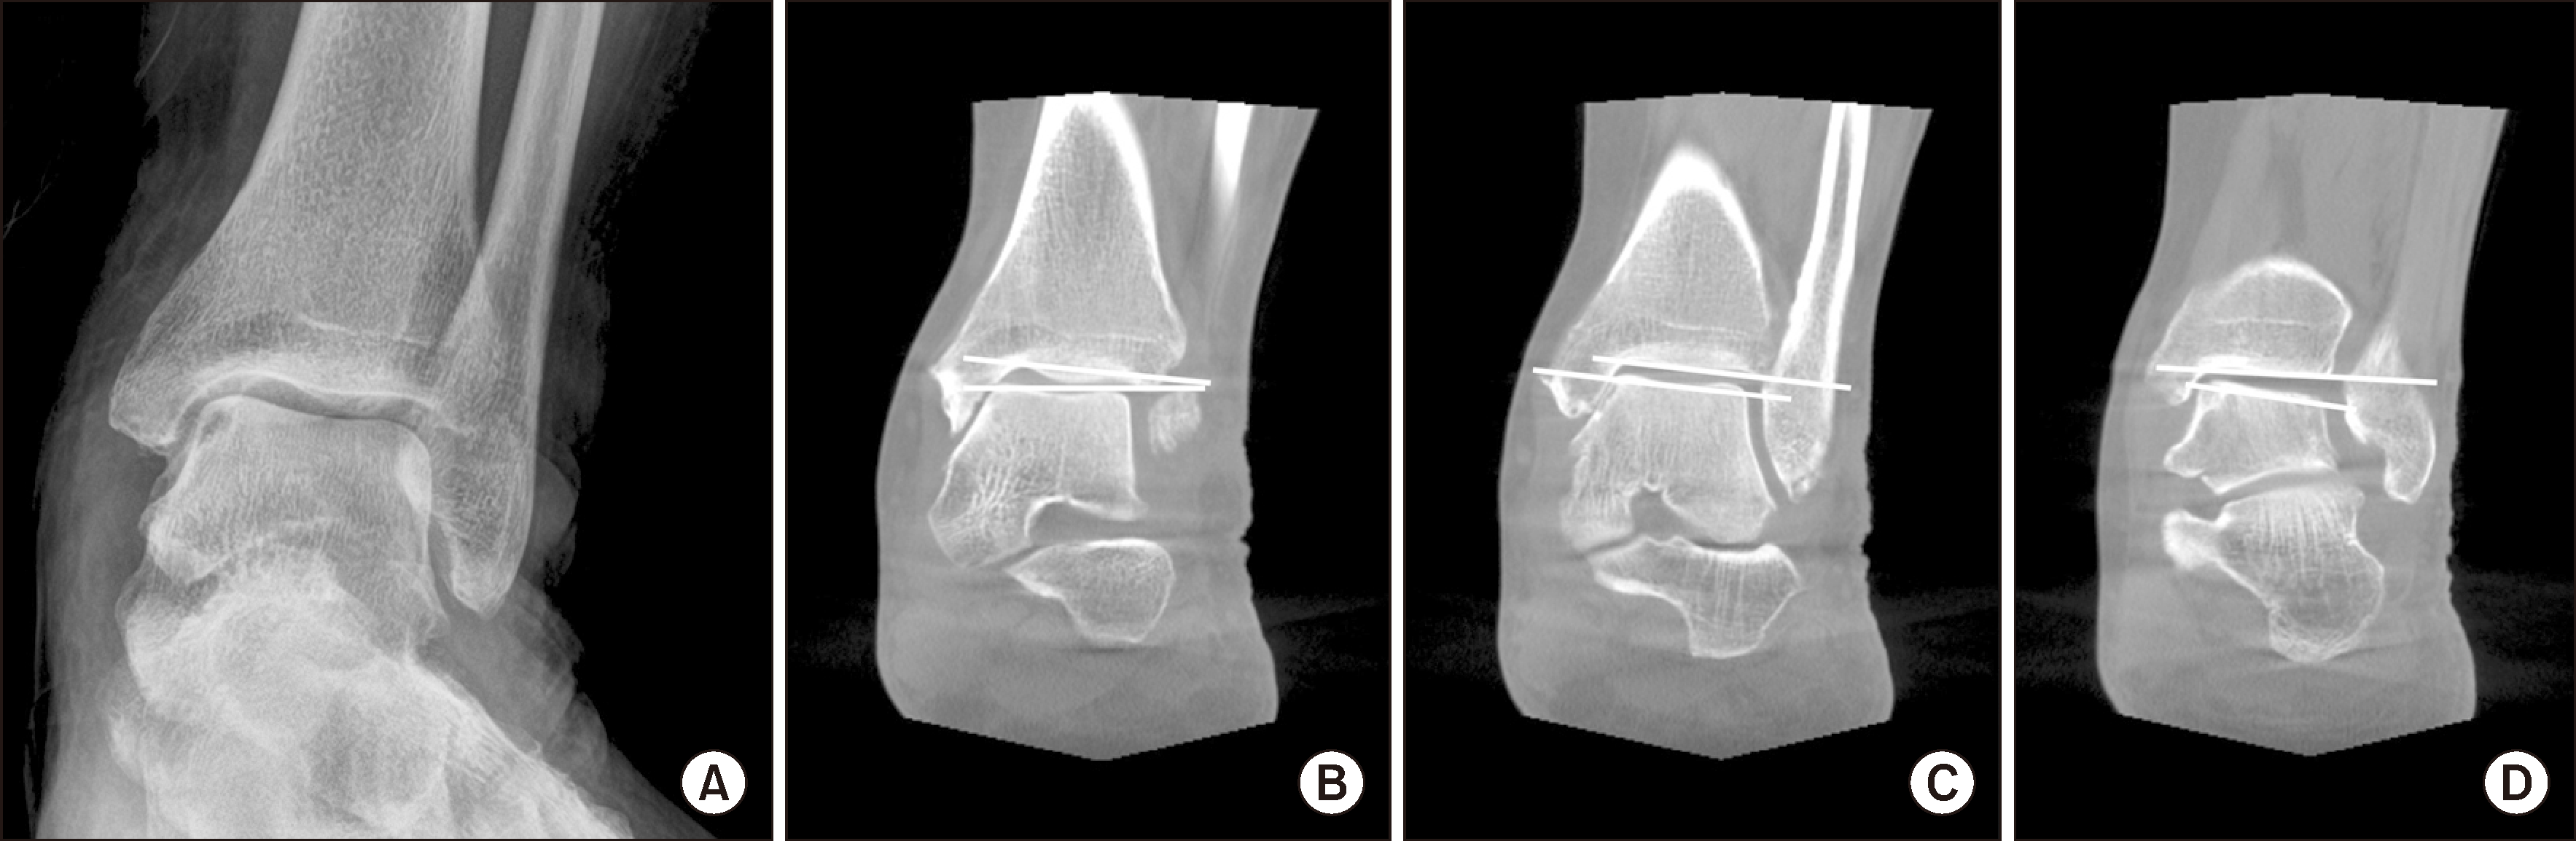

발목 관절염에서 많이 사용되고 있는 Takakura 분류법은 체중부하 단순 방사선 영상을 기반으로 관상면(coronal view)에서 발목 관절염의 진행을 평가하는 방식으로, 특히 내반(varus) 관절염의 진행에 대한 병기(stage) 분류 체계로 알려져 있었다. 하지만, 단순히 2차원적 영상만을 기반으로 분류가 되므로 모든 유형의 발목 관절염을 설명하는 데 명확한 한계가 있다. 이에 대해 Kim 등9)은 발목관절의 내측 구(gutter) 관절 간격의 경-거골 관절 간격에 대한 비율이 0.5 미만인 경우 발목 내측 구 관절염(ankle medial gutter arthrisits)으로 정의하고, WBCT를 이용하여 관상면상에서 전방, 중간, 후방 발목관절의 경거골 경사각을 분석하였다. 그 결과, 발목관절의 전방부에서는 내반이 아닌 외반(valgus)의 경-거골 경사가 관찰되었는데(Fig. 3), 이는 기존의 Takakura 분류법에서 언급한 발목 내측 구 관절염이 내반 관절염(varus arthritis)의 분류에 속한다는 개념과 상충하는 결과를 나타낸다. 또한, 다른 단순 방사선 기반 분류법 역시 3차원적인 발목관절 구조를 충분히 반영하지 못한다는 한계를 시사하였다.10,11)

Figure 3

(A) Standing ankle radiograph, (B) anterior, (C) middle, (D) posterior ankle images in coronal plane of weight-bearing computed tomography.